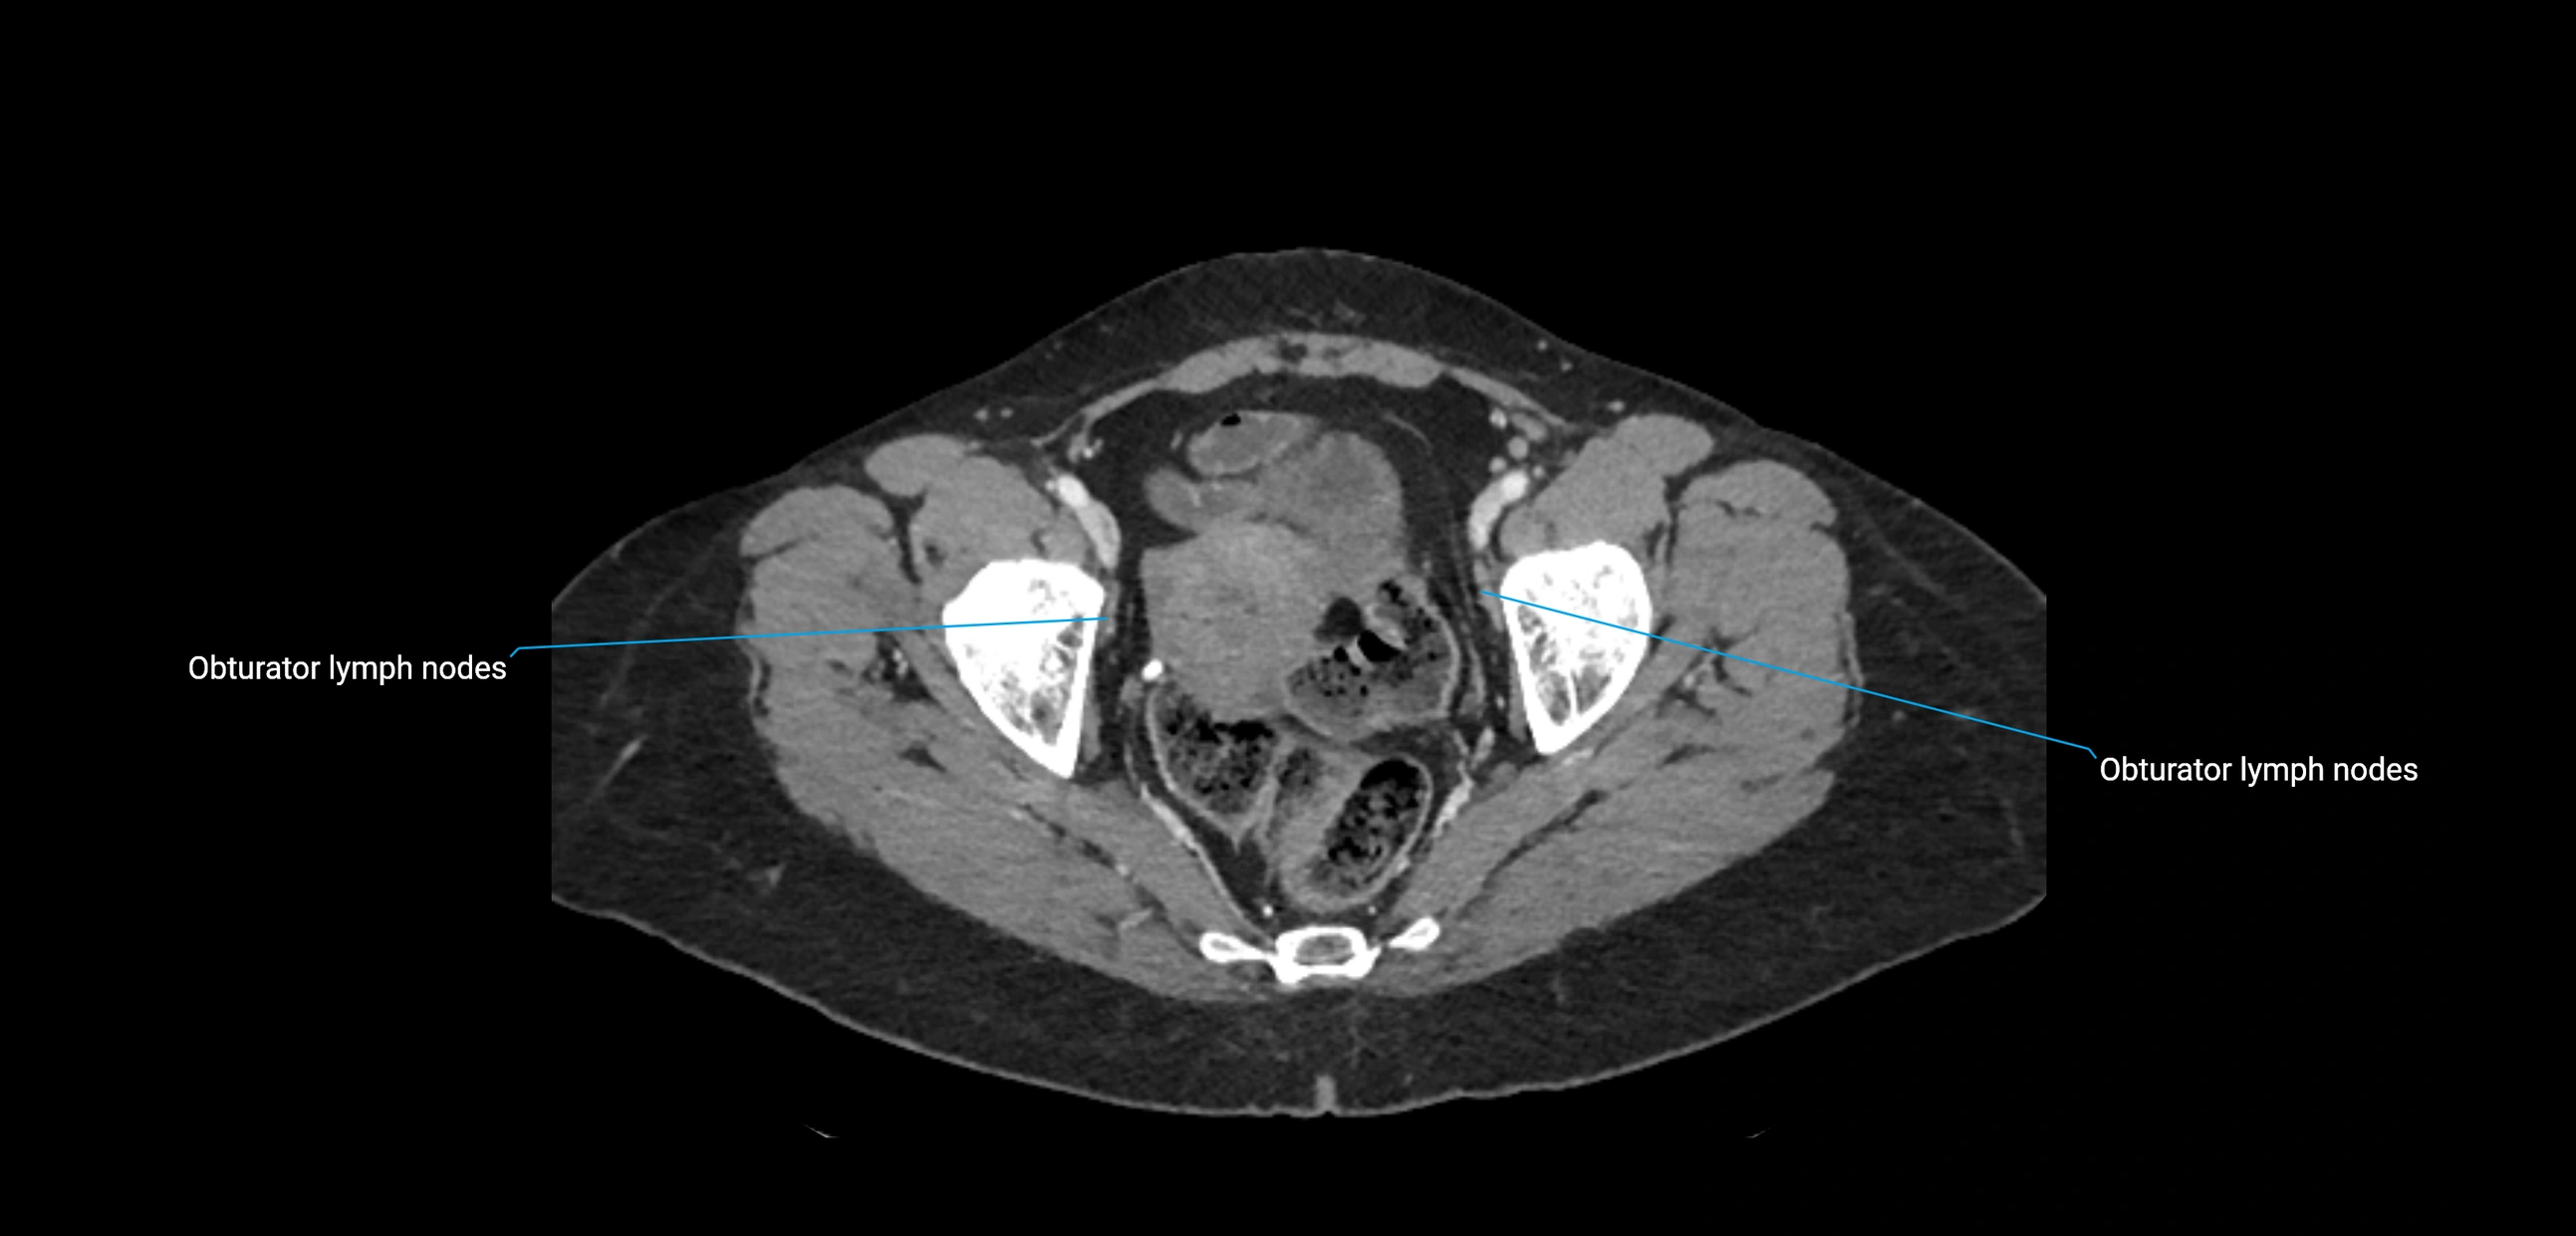

CT Appearance

CT Pre-Contrast:

• Nodes appear as soft-tissue density nodules adjacent to the aorta and IVC

• Calcification may be seen in chronic infections (e.g., tuberculosis)

CT Post-Contrast:

• Normal nodes enhance homogeneously

• Malignant nodes may show heterogeneous enhancement, central necrosis, or conglomerate formation

• Size >1 cm short axis is suspicious, though morphology and distribution are equally important